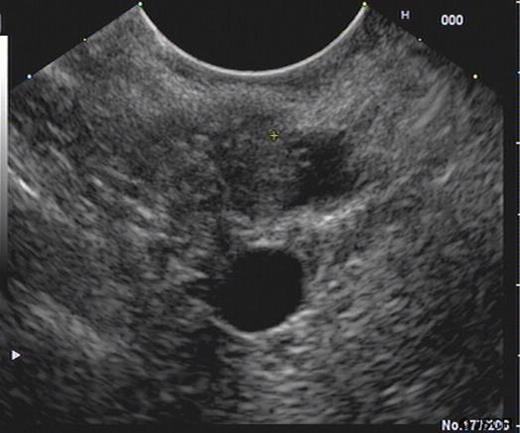

An ultrasound prior to this clinic appointment revealed a dilated Common Bile Duct (CBD) of up to 10mm, a distended thin walled gallbladder, no calculi and a normal pancreatic body. The head of the pancreas was not visualised. Laboratory tests from the GP revealed an elevated bilirubin of 150 umol/L. The CT of his abdomen and pelvis confirmed a dilated CBD and some areas of focal calcification on the head of the pancreas (Figure 3). The EUS demonstrated a thickened distal CBD with a 1.5cm hypoechoic lesion in the pancreatic head (Figure 4). The HPB MDT meeting suspected a malignant lesion and felt that a Whipple’s procedure would offer the best chance of cure.

EUS demonstrating lesion at the pancreatic head with thickening of distal CBD